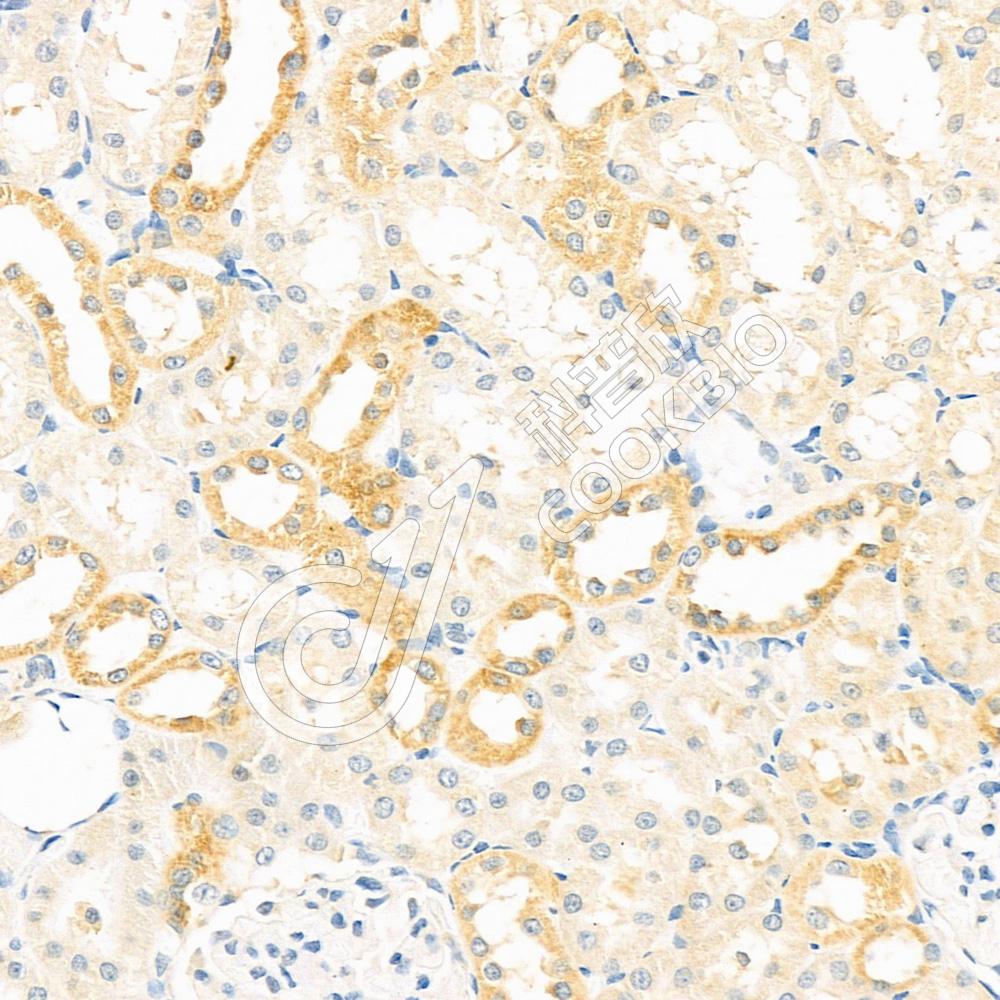

IHC检测Adenosine A2b Receptor/ADORA2B蛋白(货号 K1336783).

样品: 大鼠肾, 4%多聚甲醛 (货号KSG1101) 固定12-24小时.

抗原修复: 柠檬酸抗原修复液(干粉, pH 6.0) (KSG1201), 98℃, 20分钟.

—抗: 1: 400稀释, 4℃ 孵育过夜.

二抗: S-vision免疫组化多聚二抗(山羊抗兔),即用型 (货号KB3906), 室温孵育20分钟.